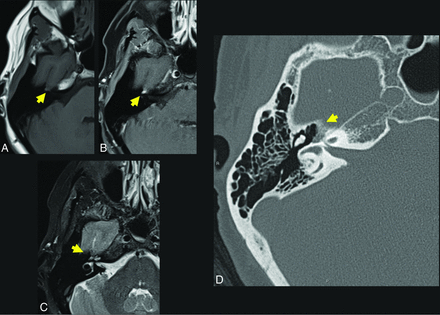

A 57-year-old woman who presented with right facial synkinesis. Noncontrast T1WI (A) and contrast-enhanced T1WI (B) demonstrate an enhancing lesion centered at the level of the right FN hiatus (yellow arrow, A and B), with corresponding increased signal on T2WI (C, yellow arrow indicates lesion). Differential considerations included both schwannoma and IOVM of the FN. Axial (D) thin-section CT of the temporal bone demonstrates an expansile, lucent lesion at the level of the anterior genu of the FN and FN hiatus (yellow arrow, D). The internal trabeculae help to confirm the diagnosis of IOVM because schwannoma would be less likely to show internal calcification. The diagnosis of IOVM was confirmed on pathology.